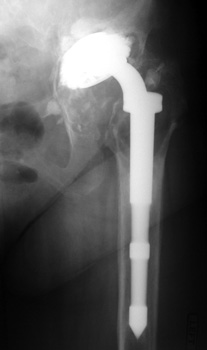

Severe polyethylene liner wear with associated osteolysis of ischium and proximal femur